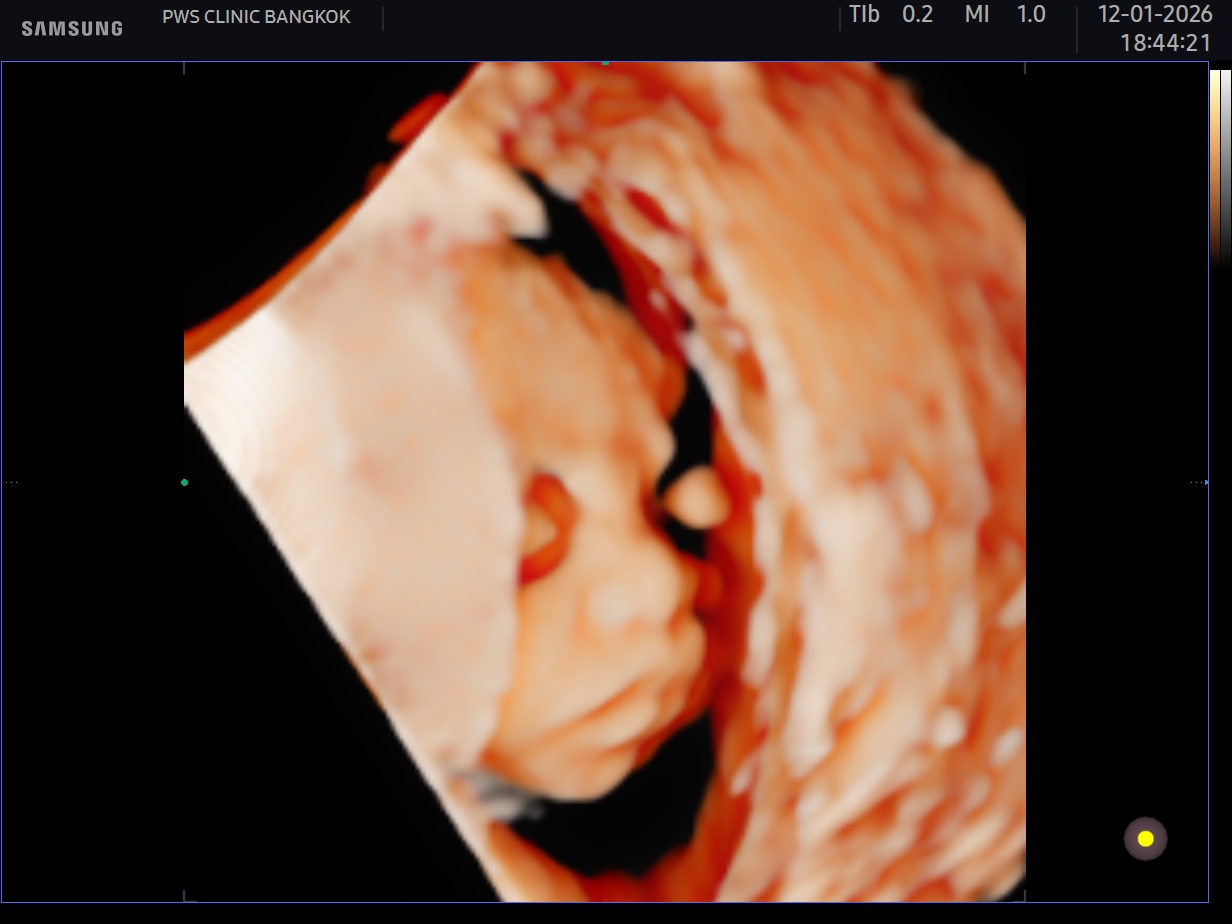

อัลตร้าซาวด์ 4 D คลอดมา หน้าตาลูกตรงกับอัลตร้าซาวด์ไหมคะ?

ในใบอัลตร้าซาวด์ คือ 25wk ค่ะ หมอบอกจมูกสวย ปากสวย

เลยอยากถาม ประสบการณ์แม่ๆว่า คลอดมาจะตรงกับใบอัลตร้าซาวด์ไหมคะ ส่วนตัวรู้สึก ในใบอัลตร้าซาวด์ลูกจมูกออกใหญ่🤣

แต่ไม่ติดอะไรค่ะ ขอแค่สมบูรณ์ แข็งแรง🥰